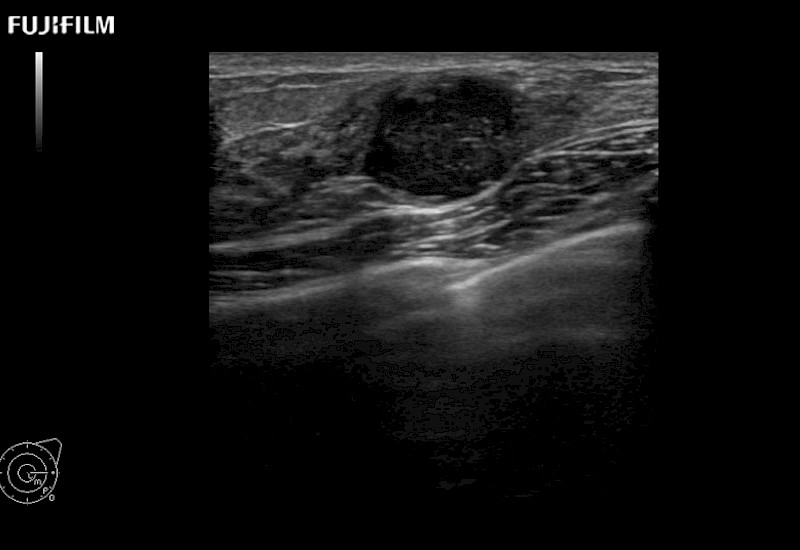

The ARIETTA 750 incorporates all of the proven technologies and functions that medical professionals have come to expect from Fujifilm Healthcare.

ARIETTA 750 is the definitive diagnostic ultrasound solution for any clinical setting - Private Office, Imaging Center, or Hospital. The ARIETTA platform provides the ultimate in clinical performance with its state-of-the-art features and large user-friendly display.

The ARIETTA 650 DI combines trusted Fujifilm Healthcare technologies and features tailored for surgical oncology.

Designed to meet the demands of surgeons, the ARIETTA 650 DI offers precise guidance. Its advanced capabilities and large, intuitive display offer accurate and efficient care in operating rooms and specialized surgical settings.